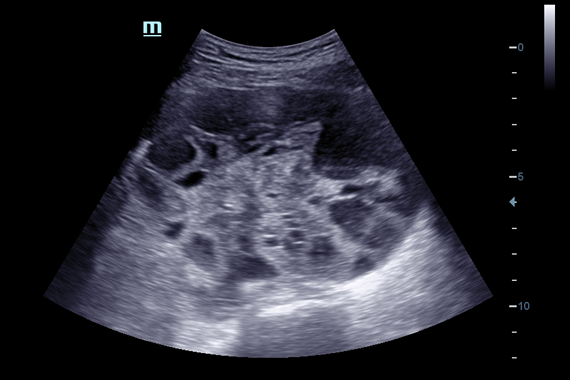

Система ультразвукового исследования Mindray DC-60 EXP X-INSIGHT является новейшей разработкой для проведения комплексных обследований на высшем уровне. Она обеспечивает решение самых сложных задач в таких областях, как кардиология, акушерство и гинекология, сосудистые заболевания, педиатрия и многие другие.

DC-60 EXP X-INSIGHT - это современный стационарный УЗИ-аппарат с функцией сенсорного управления и очищенной гармонической визуализацией, обеспечивающей лучшее контрастное разрешение и технологию 4D-визуализации. Он оснащен 21,5-дюймовым монитором, который может поворачиваться на 180 градусов, что удовлетворяет потребности врачей в качественной ультразвуковой диагностике.

• Набор услуг Shared Service Package, который включает предустановленные параметры, аннотации, маркеры, программы измерений для различных исследований, включая абдоминальные, акушерские, гинекологические, кардиологические, ангиологические, исследования малых органов, урологические, педиатрические и неотложные случаи.